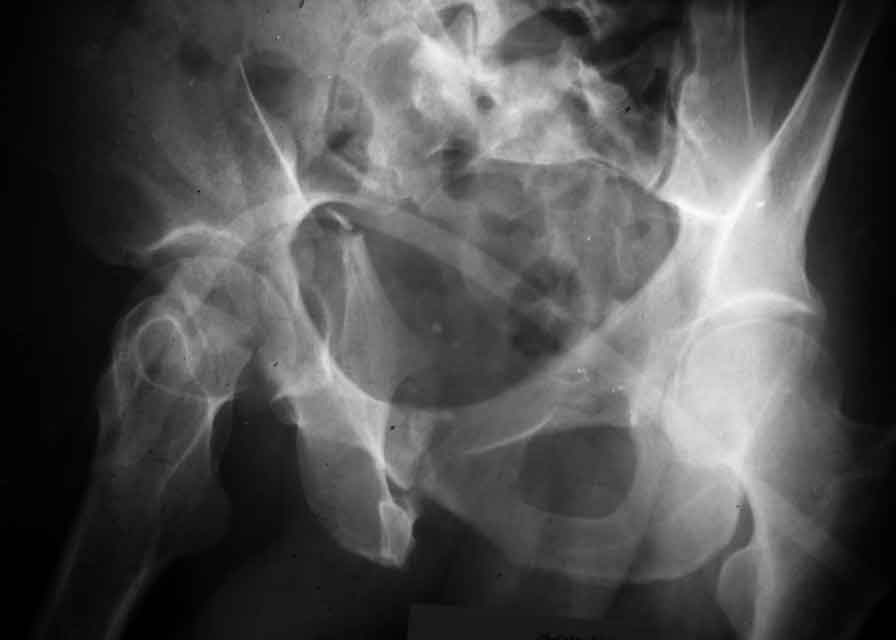

In my opinion it is a column fracture because the obturator foramen is interrupted. There is a fracture of the posterior wall. If we assume the ap view as an iliac view it could be an anterior comun fracture plus posterior wall. It is difficult also to judge the head of the femur.

From the x rays it appears like a bicolumnar fracture with iliac extension (AO C1).

I am sending another iliac view, and a marked version of the AP I already sent. In this AP, the

proximal part of the greater sciatic notch as well as the distal parts of the ilioischial and iliopubic lines are marked with a grey interrupted line. A white interrupted line marks what could be an exit through the obturator foramen, or so I assume.